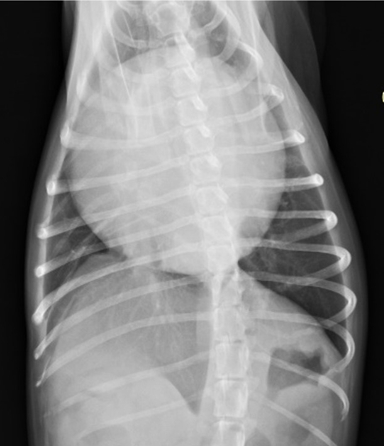

胸腔x光評估胸腔有無團塊,心臟大小;如果有心包囊積液,心臟會呈現圓且大的型態 (球形)。心臟超音波下評估心臟功能,心臟內外有無團塊樣組織,有無心包囊積液。

圖左為 患犬無心包囊積液時的心臟

圖右為 同一隻患犬心包囊積液後,